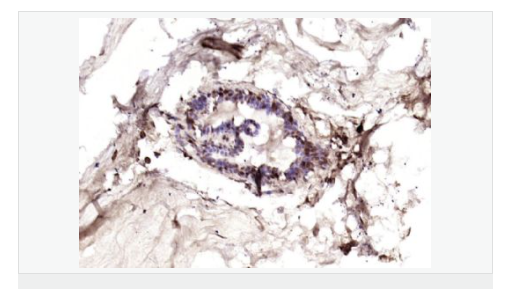

產(chǎn)品應(yīng)用ELISA=1:5000-10000 IHC-P=1:100-500 IHC-F=1:100-500 IF=1:100-500 (石蠟切片需做抗原修復(fù))

細(xì)胞定位細(xì)胞核 細(xì)胞漿 細(xì)胞膜

細(xì)胞膜受體(Membrane Receptors) c-erbB-4蛋白過(guò)去一直為乳腺癌基因研究的主要方向,研究乳腺癌組織學(xué)分級(jí)及術(shù)后生存期的關(guān)系。目前認(rèn)為他與細(xì)胞增殖活性和激素受體有一定的關(guān)聯(lián),有學(xué)者將c-erbB-4蛋白研究用于神經(jīng)內(nèi)分泌蛋白為主。